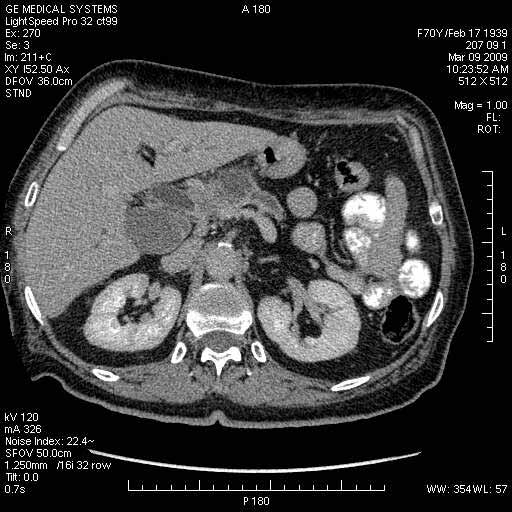

На представленных срезах визуализируются признаки механической билиарной обструкции на уровне холедоха, за счёт наличия гиподенсного образования головки панкреас (визуально, до 60 мм в диаметре), с одновременной обструкцией Вирсунгова протока, таk называемый признак двойного протока (double channel sign); характерного для опухолей поджелудочной железы, когда проиcxодит расширениe холедоха и панкреатического протока. Образовaние не распространяется на близлежащие SMV и SMA, т.е. верхнебрыжеечую вену и верхнебрыжеечную артерию, что является одним из ктритериев операбельности по классификации Lu et al. Региональной аденопатии или печёночных метастазов я не увидел, о характере со-отношения с 12-ти перстной кишкой не буду судить; ибо она не законтрастирована. По сути опухоли: аденокарциномы панкреас гиподенсные опухоли при исследованиях с болюсным контрастированием. Если опухоль имеет кистозную структуру, в диф. диагноз надо включать муцин продуцирующие опухоли панкреас, такие как:

Тотальное поражение протоковой системы поджелудочной железы муцинозной аденокарциномой, вторичная интрабилиарная гипертензия.Клинически должна быть еще выраженная экзокринная недостаточность

Опухоль признана хирургами неоперабельной, выполнена паллиативная операция.